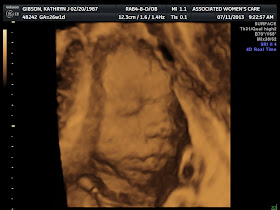

- I know I said this at 26 weeks but her movements! So fun. I used to have to lie on my back to see them, now I can see her moving while I am sitting, standing, laying down. It's so much fun (did I already say that?). My OB taught me how to feel and figure out how she is positioned (I'm a dummy and I just cannot tell), so we do that every once in a while. Passing kick counts with flying colors and kicking me in the boobs still. The dog pounced at my belly once and she kicked him back. So cute!